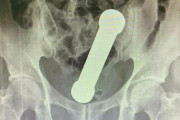

【海外】2kgのダンベルが尻から抜けなくなった男性 医師に手をつっこまれ摘出される羽目に なお入った原因は不明ーブラジル